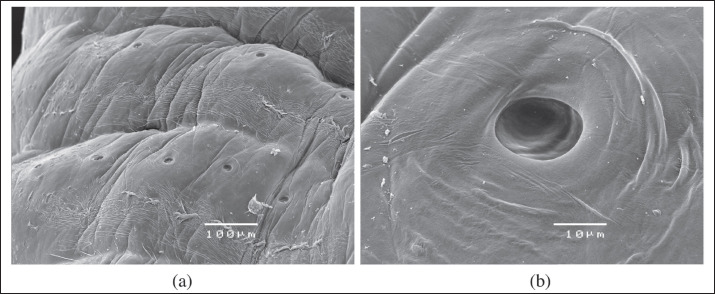

The cephalic central part and caudal parts of the adult were then dissected and examined using SEM (JEOL JSM 5410SEM). To obtain SEM images, the samples were washed in 70% ethanol and dehydrated using an ethanol graduated series. The alcohol has been replaced by liquid CO2 which, through the drying procedure at the critical point, has passed from the liquid state to the gaseous state. The dried samples were mounted on the stubs using double-sided conductive tape. The samples were metalized with a layer of gold of about 10 nm using the "sputtering." Finally, the samples were observed at the SEM Jeol JSM-5410 equipped with the Jeol SemAfore system for image acquisition. SEM photographs showed that the mouth was rounded, measured 3.78 × 4.03 µm, and was surrounded by a chitinous buccal cadre, while the four hooks were slightly curved and had a sharp tip (Fig. 3A and B). Each annulus had a row of pores (chloride cell caps) located on the upper part (Fig. 4A and B). A distinct terminal cleft was present at the posterior tip (Fig. 5A and B). The uterus filled with thousands of embryonating eggs was clearly visible (Fig. 6A). SEM also highlighted some morphological characteristics of the L. serrata eggs: though the egg shell appears to be smooth (Fig. 6B and C), as seen by stereomicroscopy, the surface presents irregularly distributed small pits, which give the eggs a slightly porous heterogeneous appearance (Fig. 5).

Fig. 4. SEM of the sensory pore structure of the annuli of a female L. serrata specimen (A: scale bar 100 μ; B: scale bar 10 μ).